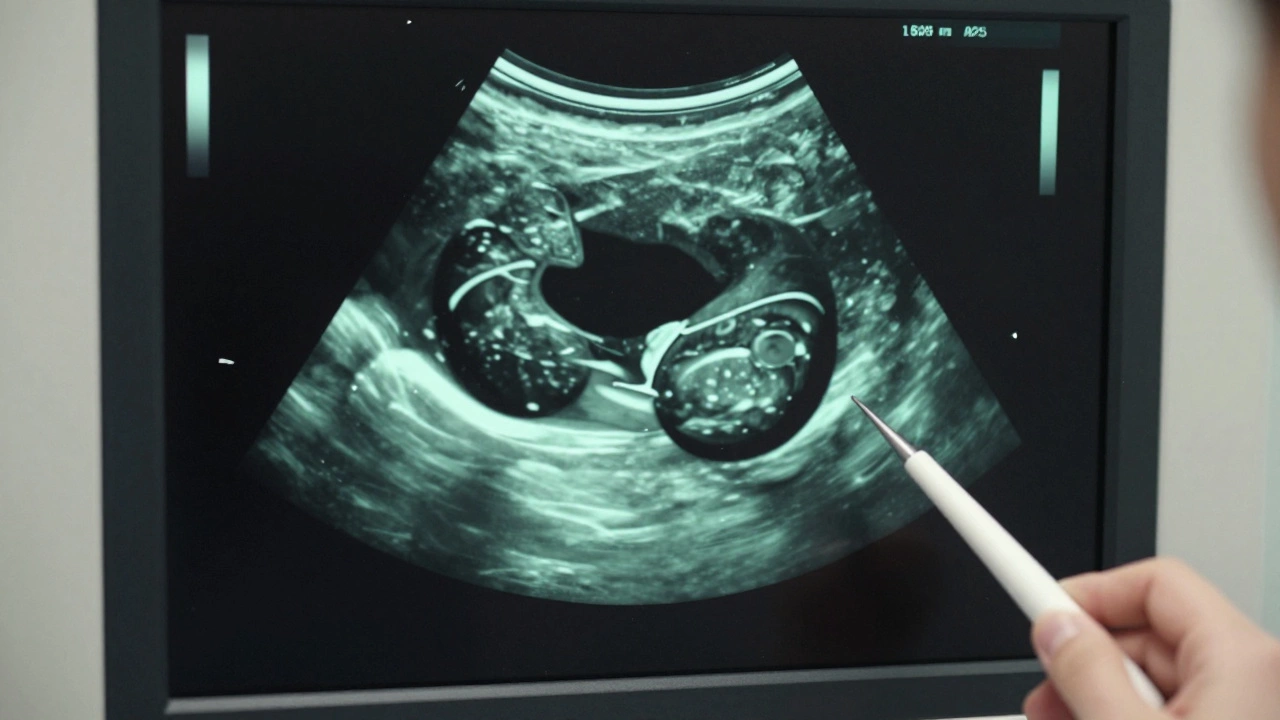

УЗИ-изображение кисты яичника как темного овала с ровными краями.

Врач не ставит диагноз по ощущениям. Он использует инструменты. Первое, что назначат - УЗИ. Это безопасно, быстро, без боли. На УЗИ киста выглядит как чёткое, тёмное пятно с ровными границами. Жидкость внутри не отражает звук - поэтому она чёрная на экране. Если киста плотная, с внутренними перегородками или содержит твёрдые включения - врач заподозрит нечто другое и назначит дополнительные анализы.